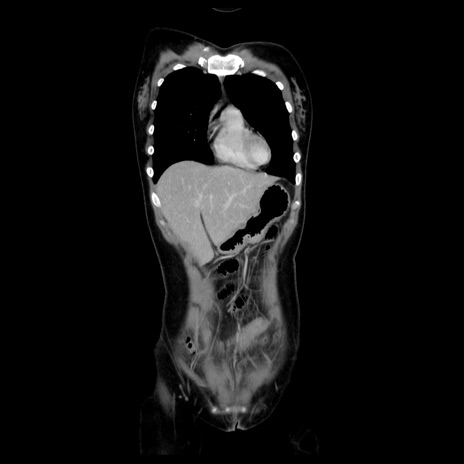

症例39(冠状断像)

【症例】40歳代女性

【主訴】上下腹部痛

【現病歴】2日目から下腹部痛あり。夜間は痛みで眠れなかった。昨日より上腹部痛と下痢が出現。臥位で痛みは軽快したため、休んでいた。本日になって臥位でも立位でも痛みが強くなってきたため救急要請。

【既往歴】子宮内膜症

【身体所見】部:平坦・軟、左上下腹部に圧痛あり、反跳痛あり。

【データ】WBC 21800、CRP 26.78

CT